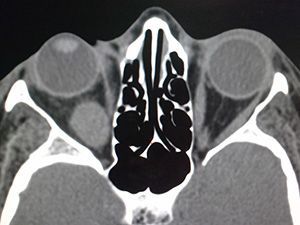

КТ орбит глаза

Компьютерная томография орбиты глаза проводится с целью уточнения диагноза при подозрении на наличие патологии данной зоны. Она позволяет получить данные о:

• наличии/отсутствии новообразований на самых ранних стадиях;

• состоянии глаз и параорбитальных областей.

По результатам КТ орбит врач составляет план лечения выявленного заболевания или назначает оперативное вмешательство. Данная процедура отличается высокой информативностью и оказывает минимальную лучевую нагрузку на организм пациента.

КТ орбит может проводиться с применением йодсодержащего контрастного вещества.